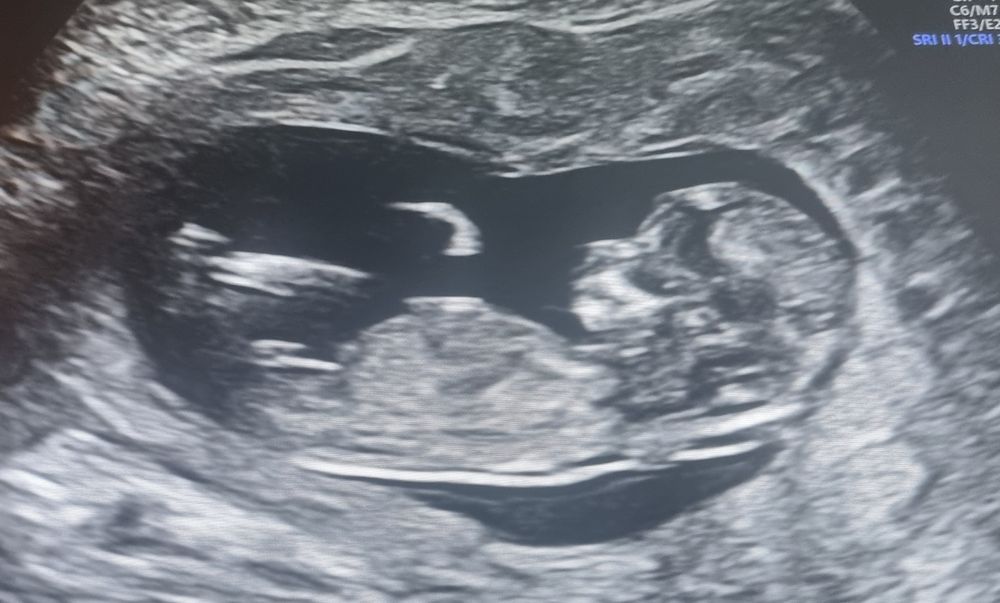

Кира, по профилю просто личико миниатюрное такое, поэтому и подумала))) Изображениевот у меня доча в 12+6 недель)

Алёна Хаустова, какая малышка❤️❤️❤️